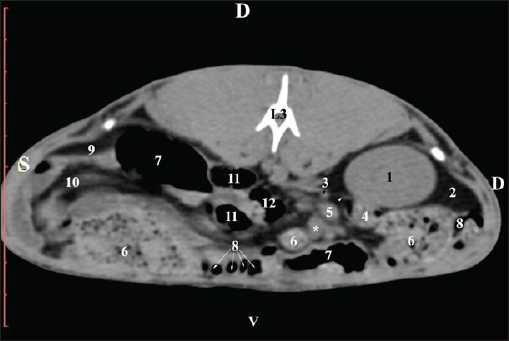

Fig. 5. Pre-contrast computed tomography (CT) anatomical scan of the regio-abdominis media at the caudal L2 edge level. (1) Ren dexter; (2) pelvis renalis; (3) lobus caudatus (proc. caudatus) with visceral adipose tissue; (4) gl. adrenalis dextra; (5) ileum; (6) jejunum; (7) colon ascendens; (8) cecum; (9) colon transversum; (10) colon descendens; (11) lien; (*) ureter; (white arrow) recessus renalis. At the L3 level, the anatomical adjacencies of the right kidney with the pars descendens of the duodenum, ileum, cecum, and colon descendens were visualized. Hypoattenuated right ureter and normoattenuated gl. adrenalis dextra were situated medially to the right kidney. Extremitas caudalis of the right kidney was a clearly visible normoattenuated finding, surrounded by hypoattenuated borders of abdominal adipose collections (Figs. 6 and 7).

Fig. 6. Pre-contrast CT anatomical scan of the regio-abdominis media at the cranial L3 edge level. (1) Ren dexter; (2) lobus caudatus (proc. caudatus) with visceral adipose tissue; (3) gl. adrenalis dextra; (4) pars descendens of the duodenum; (5) ileum; (6) cecum; (7) colon ascendens; (8) jejunum; (9) lien; (10) colon ascendens; (11) colon transversum; (12) colon descendens, (*) mesenterium.